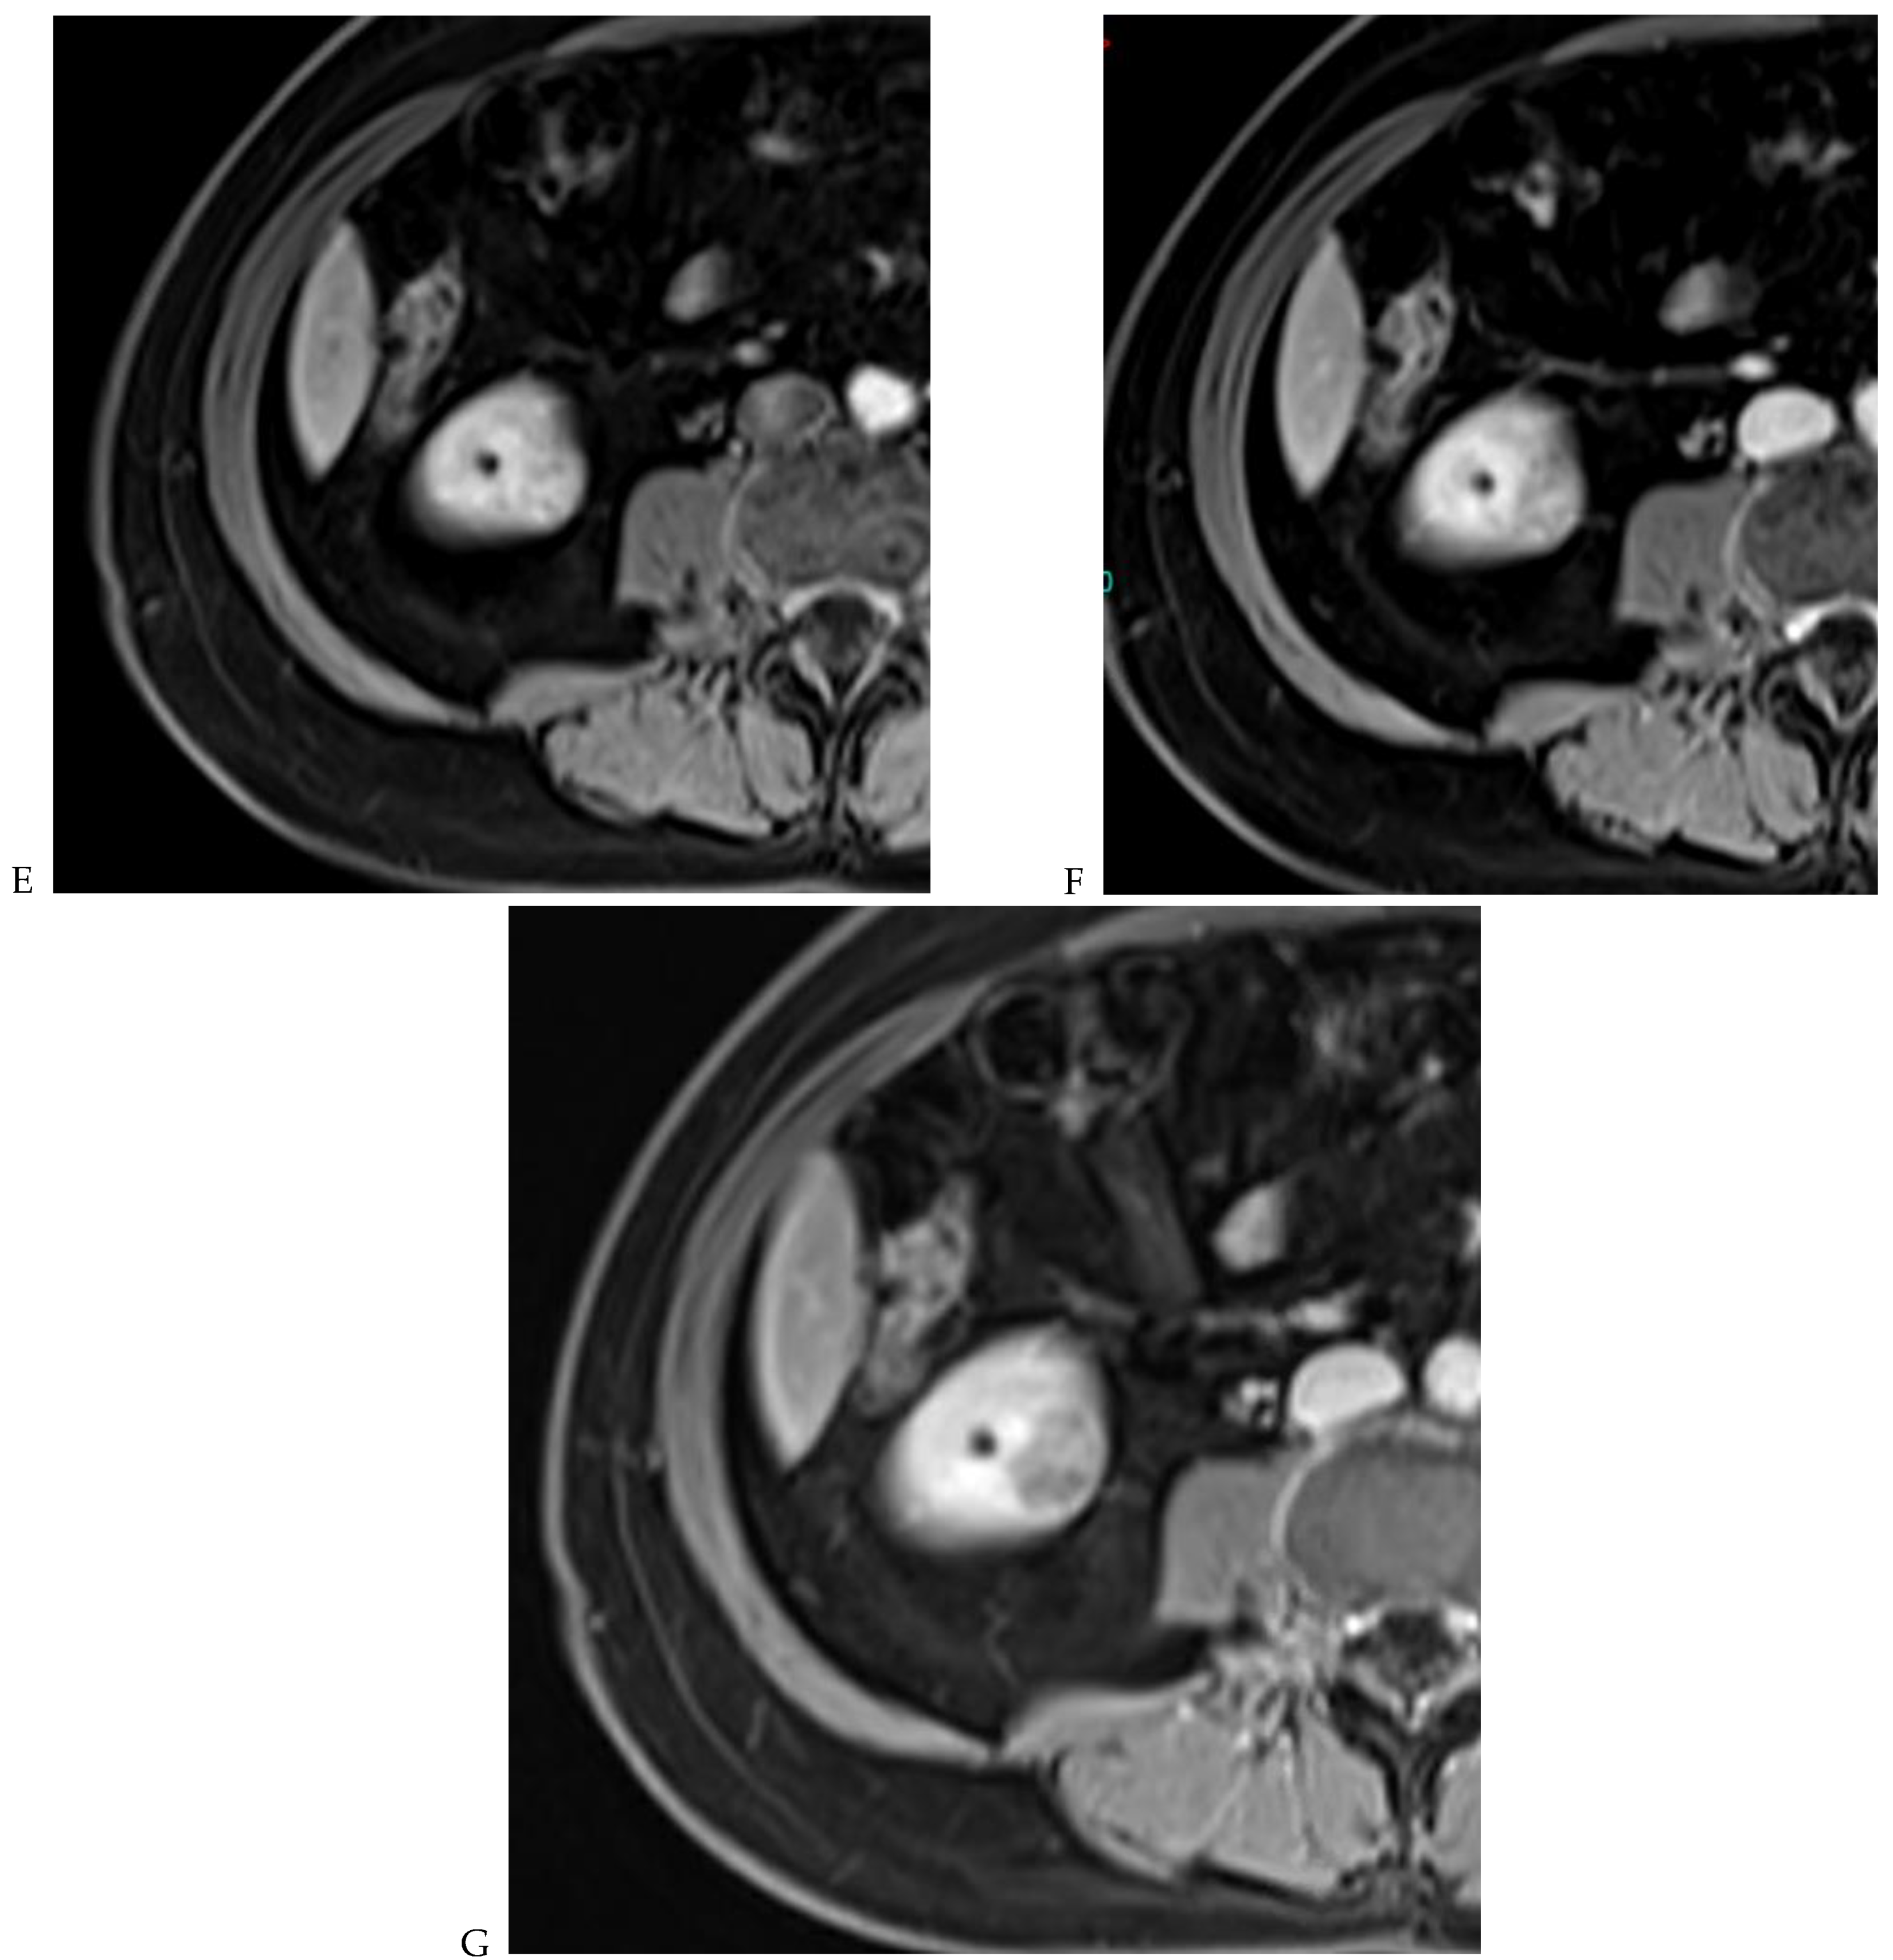

Figure 7.

Papillary renal cell carcinoma in the right kidney of a 75-year-old-woman. (A) Axial T2-weighted fast SE image shows a homogeneous 1.8 cm mass in the posterolateral region of the right kidney, with a lower SI compared to renal parenchyma. Transverse in-phase (B,C) opposed-phase MR images do not show a significant signal loss on the opposed-phase image. (D) The ADC map shows restriction of tumor diffusion into the renal mass. Transverse nonenhanced (E) and gadolinium-enhanced T1-weighted gradient-echo spoiled MR images in (F) corticomedullary, (G) nephrographic, (H) and delayed phase images show progressive enhancement without washout; the mass is hypovascular compared to the renal cortex.